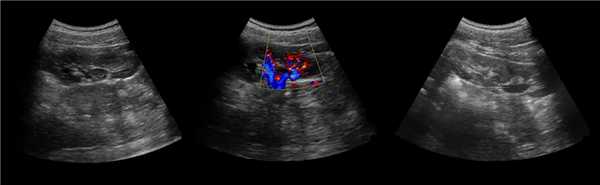

• Исследование 8 режиме серой шкалы:

о Нормальный контур почки

о Обычно изоэхогенно по отношению к корковому веществу

о Цветовое и энергетическое допплеровское картирование позволяет визуализировать поток, идентичный корковому веществу

о Разделение центральных эхосигналов

(Слева) На рисунке показано объемное расширение коркового вещества почки между верхней и средней чашечками.

(Справа) КТ, аксиальная проекция, кортико-медуллярная фаза контрастирования: дорсальная половина межполюсной области почки, контрастируемая аналогично корковому веществу почки. На последующих фазах выявлено гомогенное контрастирование почки.

Бывает колонна Бертини врезается в центральную часть почки, разделяя ее полно или неполно на две части. Такая паренхиматозная перемычка — это паренхима полюса одной из эмбриональных долек, которые сливаясь образуют почку; состоит из коры, пирамид, колонн Бертини — все элементы без признаков гипертрофии или дисплазии. Термин гипертрофия колонны Бертини не отражает морфологию структуры, точнее считать данное образование паренхиматозной перемычкой.

Рисунок. На УЗИ округлое образование разделяет почечный синус на два сегмента с общей лоханкой; междолевые артерии огибают образование; эхогенность и интенсивность сосудистого рисунка внутри близка корковой зоне. Заключение: Гипертрофия колонны Бертини или неполная паренхиматозная перемычка. Это вариант нормального строения почки. Термин «неполное удвоение ЧЛК» неверный, т.к. неполная паренхиматозная перемычка не является признаком удвоения ЧЛК.